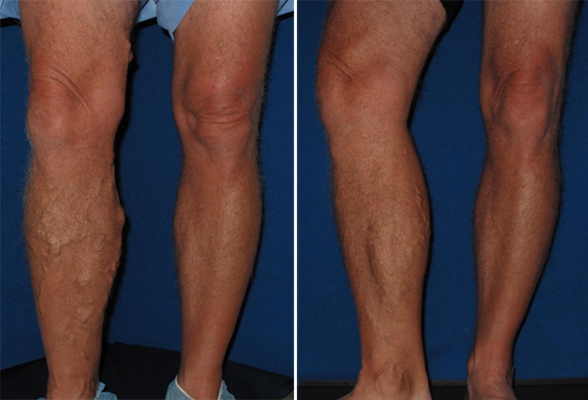

沙蚤病

沙蚤病

沙蚤病

沙蚤病

沙蚤病

沙蚤病

沙蚤病

沙蚤病

沙蚤病

沙蚤病

沙蚤病

沙蚤病

沙蚤病

沙蚤病

沙蚤病

沙蚤病

沙蚤病

沙蚤病

沙蚤病

沙蚤病

A:跳蚤一般喜歡溫暖的地方,它是吸血的昆蟲,所以一般都在人的內衣縫隙中生存和繁殖,比如內衣褲接縫的地方。所以有了跳蚤,過去都是用六六粉,在屋裡到處撒。因為六六粉對人體有毒害,所以建議用八四消毒液,可以將消毒液裝入噴壺中在屋裡噴灑,傢俱以及床周圍……